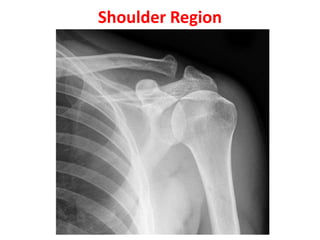

Shoulder Region

• 1st Year- Head of

humerus

• 2nd –Greater tuberosity

• 5th year- Lesser tub.

• 6th Year- Fusion of upper

end of humerus into one

mass

• FUSION

• 20th Year - Fusion of

upper end of humerus

with shaft